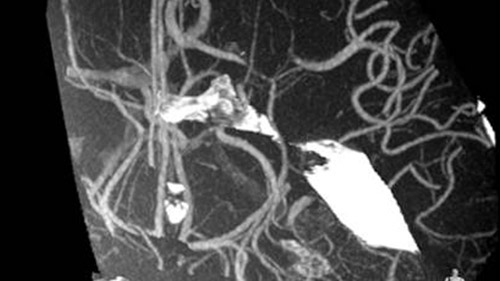

AlluraClarity motion compensation corrects for subtraction artifacts, automatically and in real-time. This is particularly important when placing small devices at the base of the skull.

2D navigation with Roadmap Pro is supported by automatic, real-time motion compensation and decreased subtraction artifacts. Clinical modes are optimized for various clinical applications.

VasoCT visualizes small intra-cranial devices in vessel context with unmatched spatial resolution. Metal Artifact Reduction decreases streaking artifacts as from coil mass close to intra-cranial devices.